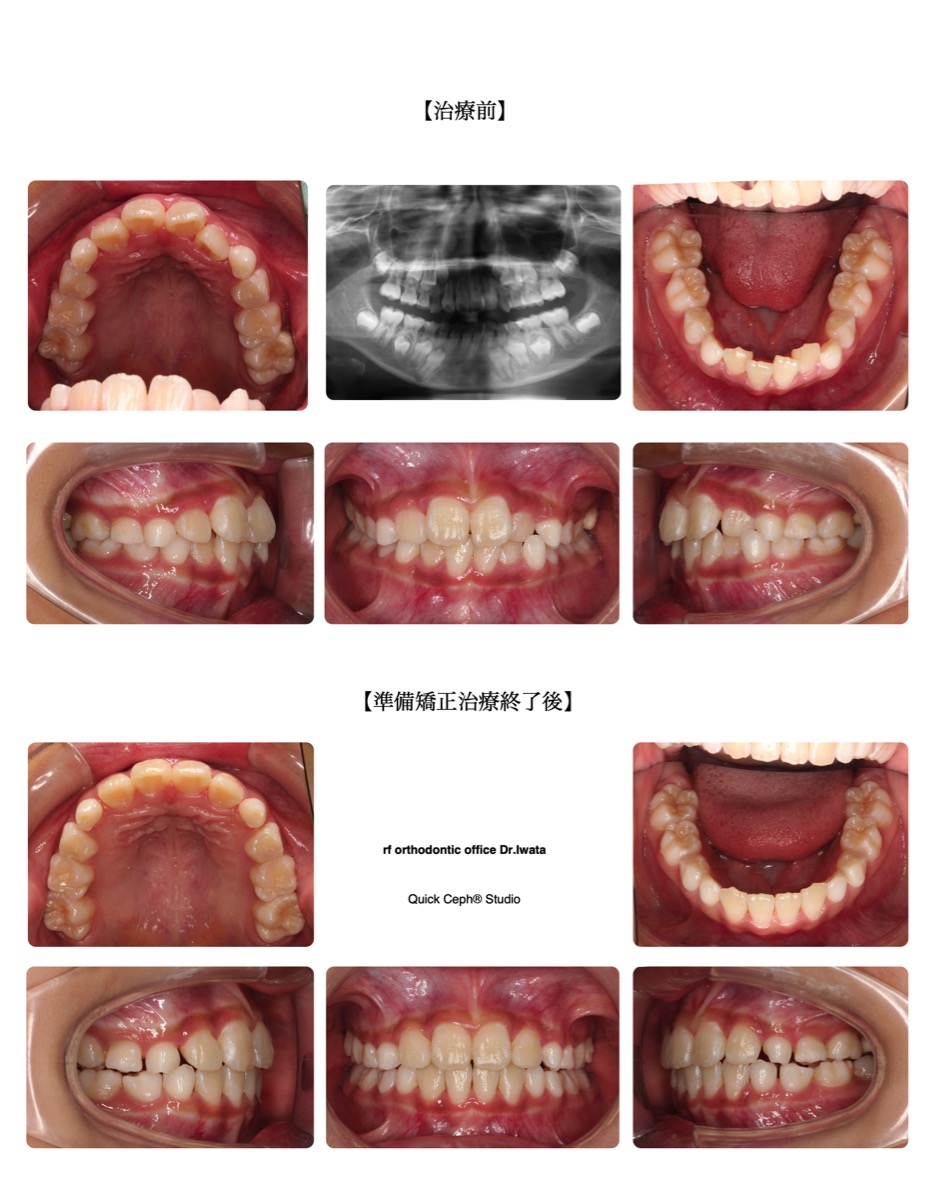

叢生症例 <歯列狭窄を伴う叢生に対する準備矯正治療>

矯正治療症例一覧

アールエフ矯正歯科で実際に治療を受けられた方の症例写真をご紹介しています。

治療前後でどのように改善されるか一目でおわかりいただけますので、

ご自身やお子さまの治療を検討されている方はぜひご参考にしてください。